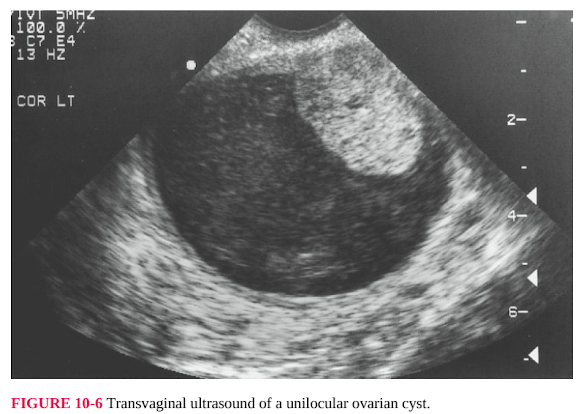

size and location of the usually multiple leiomyomas can be confirmed and

documented with pelvic ultrasonography (Fig. 10-5). If the examination is

FIGURE 10-5 Transvaginal pelvic ultrasound demonstrating multiple uterine leiomyomas.

Other studies may be necessary or appropriate. [4] The most commonly indicated

its consistency—unilocular cyst, mixed echogenicity, multiloculated cyst, or solid

mass—which can help determine management (Figs. 10-6 and 10-7). Size greater

FIGURE 10-6 Transvaginal ultrasound of a unilocular ovarian cyst.

[4] Transvaginal and transabdominal ultrasonography are complementary in the

diagnosis of pelvic masses, particularly those that have an abdominal component.

Transvaginal ultrasonography has the advantage of providing additional

information about the internal architecture or anatomy of the mass.